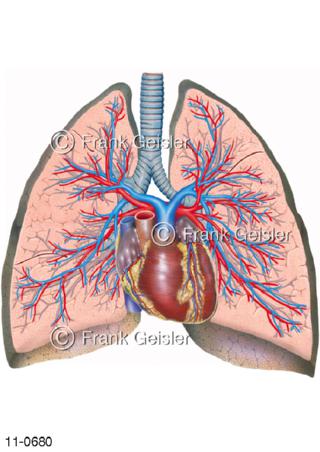

11-0680 Luftröhre, Frontalschnitt Lungen, Herz mit Lungengefäße